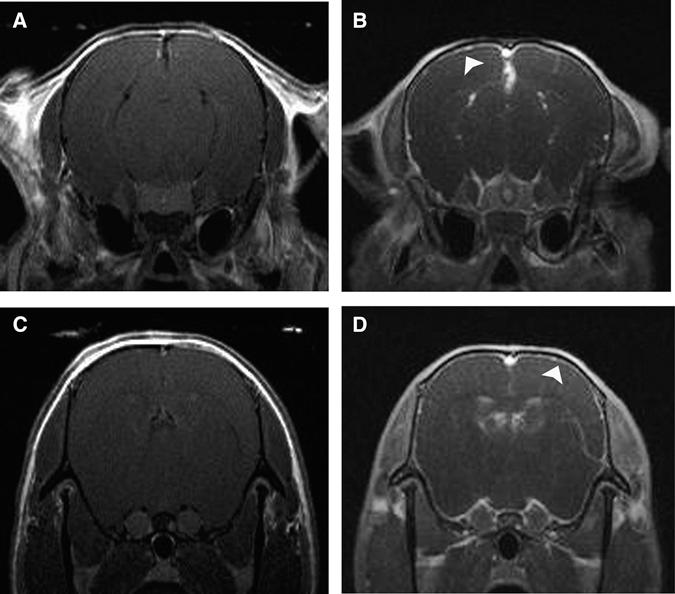

The ability of trypanosomes to invade the brain and induce an inflammatory reaction is well-recognized. This study uses magnetic resonance imaging (MRI) in conjunction with a murine model of central nervous system (CNS) stage trypanosomiasis to investigate this phenomenon at the level of the blood-brain barrier (BBB). Mice were scanned before and after administration of the contrast agent. Signal enhancement maps were generated, and the percentage signal change was calculated. The severity of the neuroinflammation was also assessed. Statistical analysis of the signal change data revealed a significantly (P = 0.028) higher signal enhancement in mice at 28 days post-infection (least squares mean = 26.709) compared with uninfected animals (6.298), indicating the presence of BBB impairment. Leukocytes were found in the meninges and perivascular space of some blood vessels in the infected mice. This study shows that the integrity of the BBB is compromised during CNS stage trypanosomiasis and that the impairment does not correlate with inflammatory cell infiltration.

锥虫侵入大脑并引发炎症反应的能力是众所周知的。本研究使用磁共振成像(MRI)结合中枢神经系统(CNS)阶段锥虫病的小鼠模型,在血脑屏障(BBB)水平上研究这一现象。在给予造影剂之前和之后对小鼠进行扫描。生成信号增强图,并计算信号变化的百分比。还评估了神经炎症的严重程度。信号变化数据的统计分析显示,感染后 28 天的小鼠(最小二乘均值= 26.709)与未感染动物(6.298)相比,信号增强显著(P = 0.028),表明存在 BBB 损伤。在感染小鼠的脑膜和一些血管的血管周围空间中发现了白细胞。这项研究表明,在中枢神经系统阶段锥虫病期间 BBB 的完整性受到损害,并且这种损害与炎症细胞浸润无关。